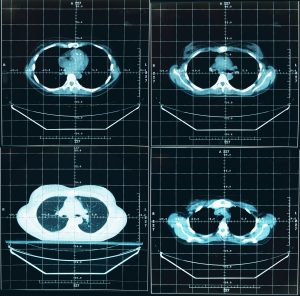

Mehr erfahren zu: "CT- Gefäßentfernungsalgorithmus verbessert die Vorhersage der Invasivität von Lungenkrebs" CT- Gefäßentfernungsalgorithmus verbessert die Vorhersage der Invasivität von Lungenkrebs Wissenschaftlern einer kürzlich im „European Journal of Radiology“ veröffentlichten Studie zufolge, kann die zusätzliche Verwendung eines Gefäßentfernungsalgorithmus (vessel removal algorithm, VRA) bei einer CT die Vorhersage der invasiven Komponente eines […]